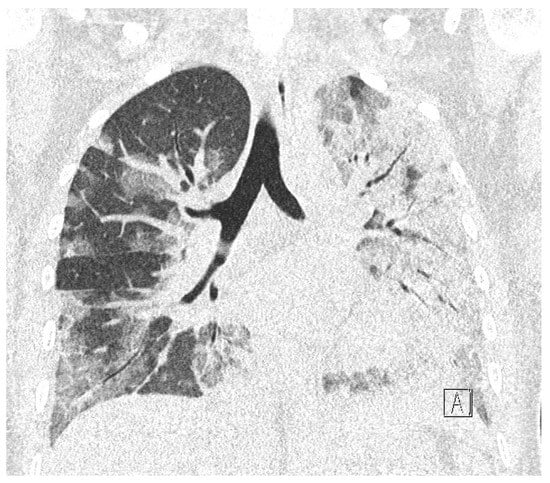

The control CTG record was normal, revealing normal cardiac activity and reactive variability (Figure 6). Laboratory tests are summarised in Table 3. Due to the symptoms of upper respiratory tract infection and elevated values of inflammatory parameters (CRP 52.50 mg/L [N: <5]), prophylactic antibiotic therapy with third-generation cephalosporin was ordered. The patient was also prescribed a prophylactic dose of low-molecular-weight heparin.

During the next two days of hospitalisation, the patient’s general condition was stable. However, in the controlled laboratory test disturbingly high concentration of D-dimer, decreased platelet level and fibrinogen values were observed (Table 3). The differential diagnosis included: haemostatic disorders in the course of COVID-19 infection, the onset of DIC. In the follow-up cardiotocographic record, tachycardia 170 bpm, minimal variability and recurrent decelerations were observed (Figure 7). Due to the development of DIC and the intrauterine foetal asphyxia, the patient was qualified for an emergency caesarean section. Before the procedure, the patient received 1 unit of platelet concentrate. The surgery was uneventful. The pelvic drainage comprised 100 mL of serous blood; therefore, it was removed on the first postoperative day. Due to anaemia (HGB 8.7%, HCT 26%) as well as weakness and dizziness reported by the patient, 2 units of packed red blood cells were transfused, which resulted in normalisation of the red blood cell system parameters.

Figure 6. Cardiotocographic record made on day 0 of hospitalisation-normal baseline, normal variability.

Figure 7. CTG record on day 2 of hospitalisation. Tachycardia, decelerations.